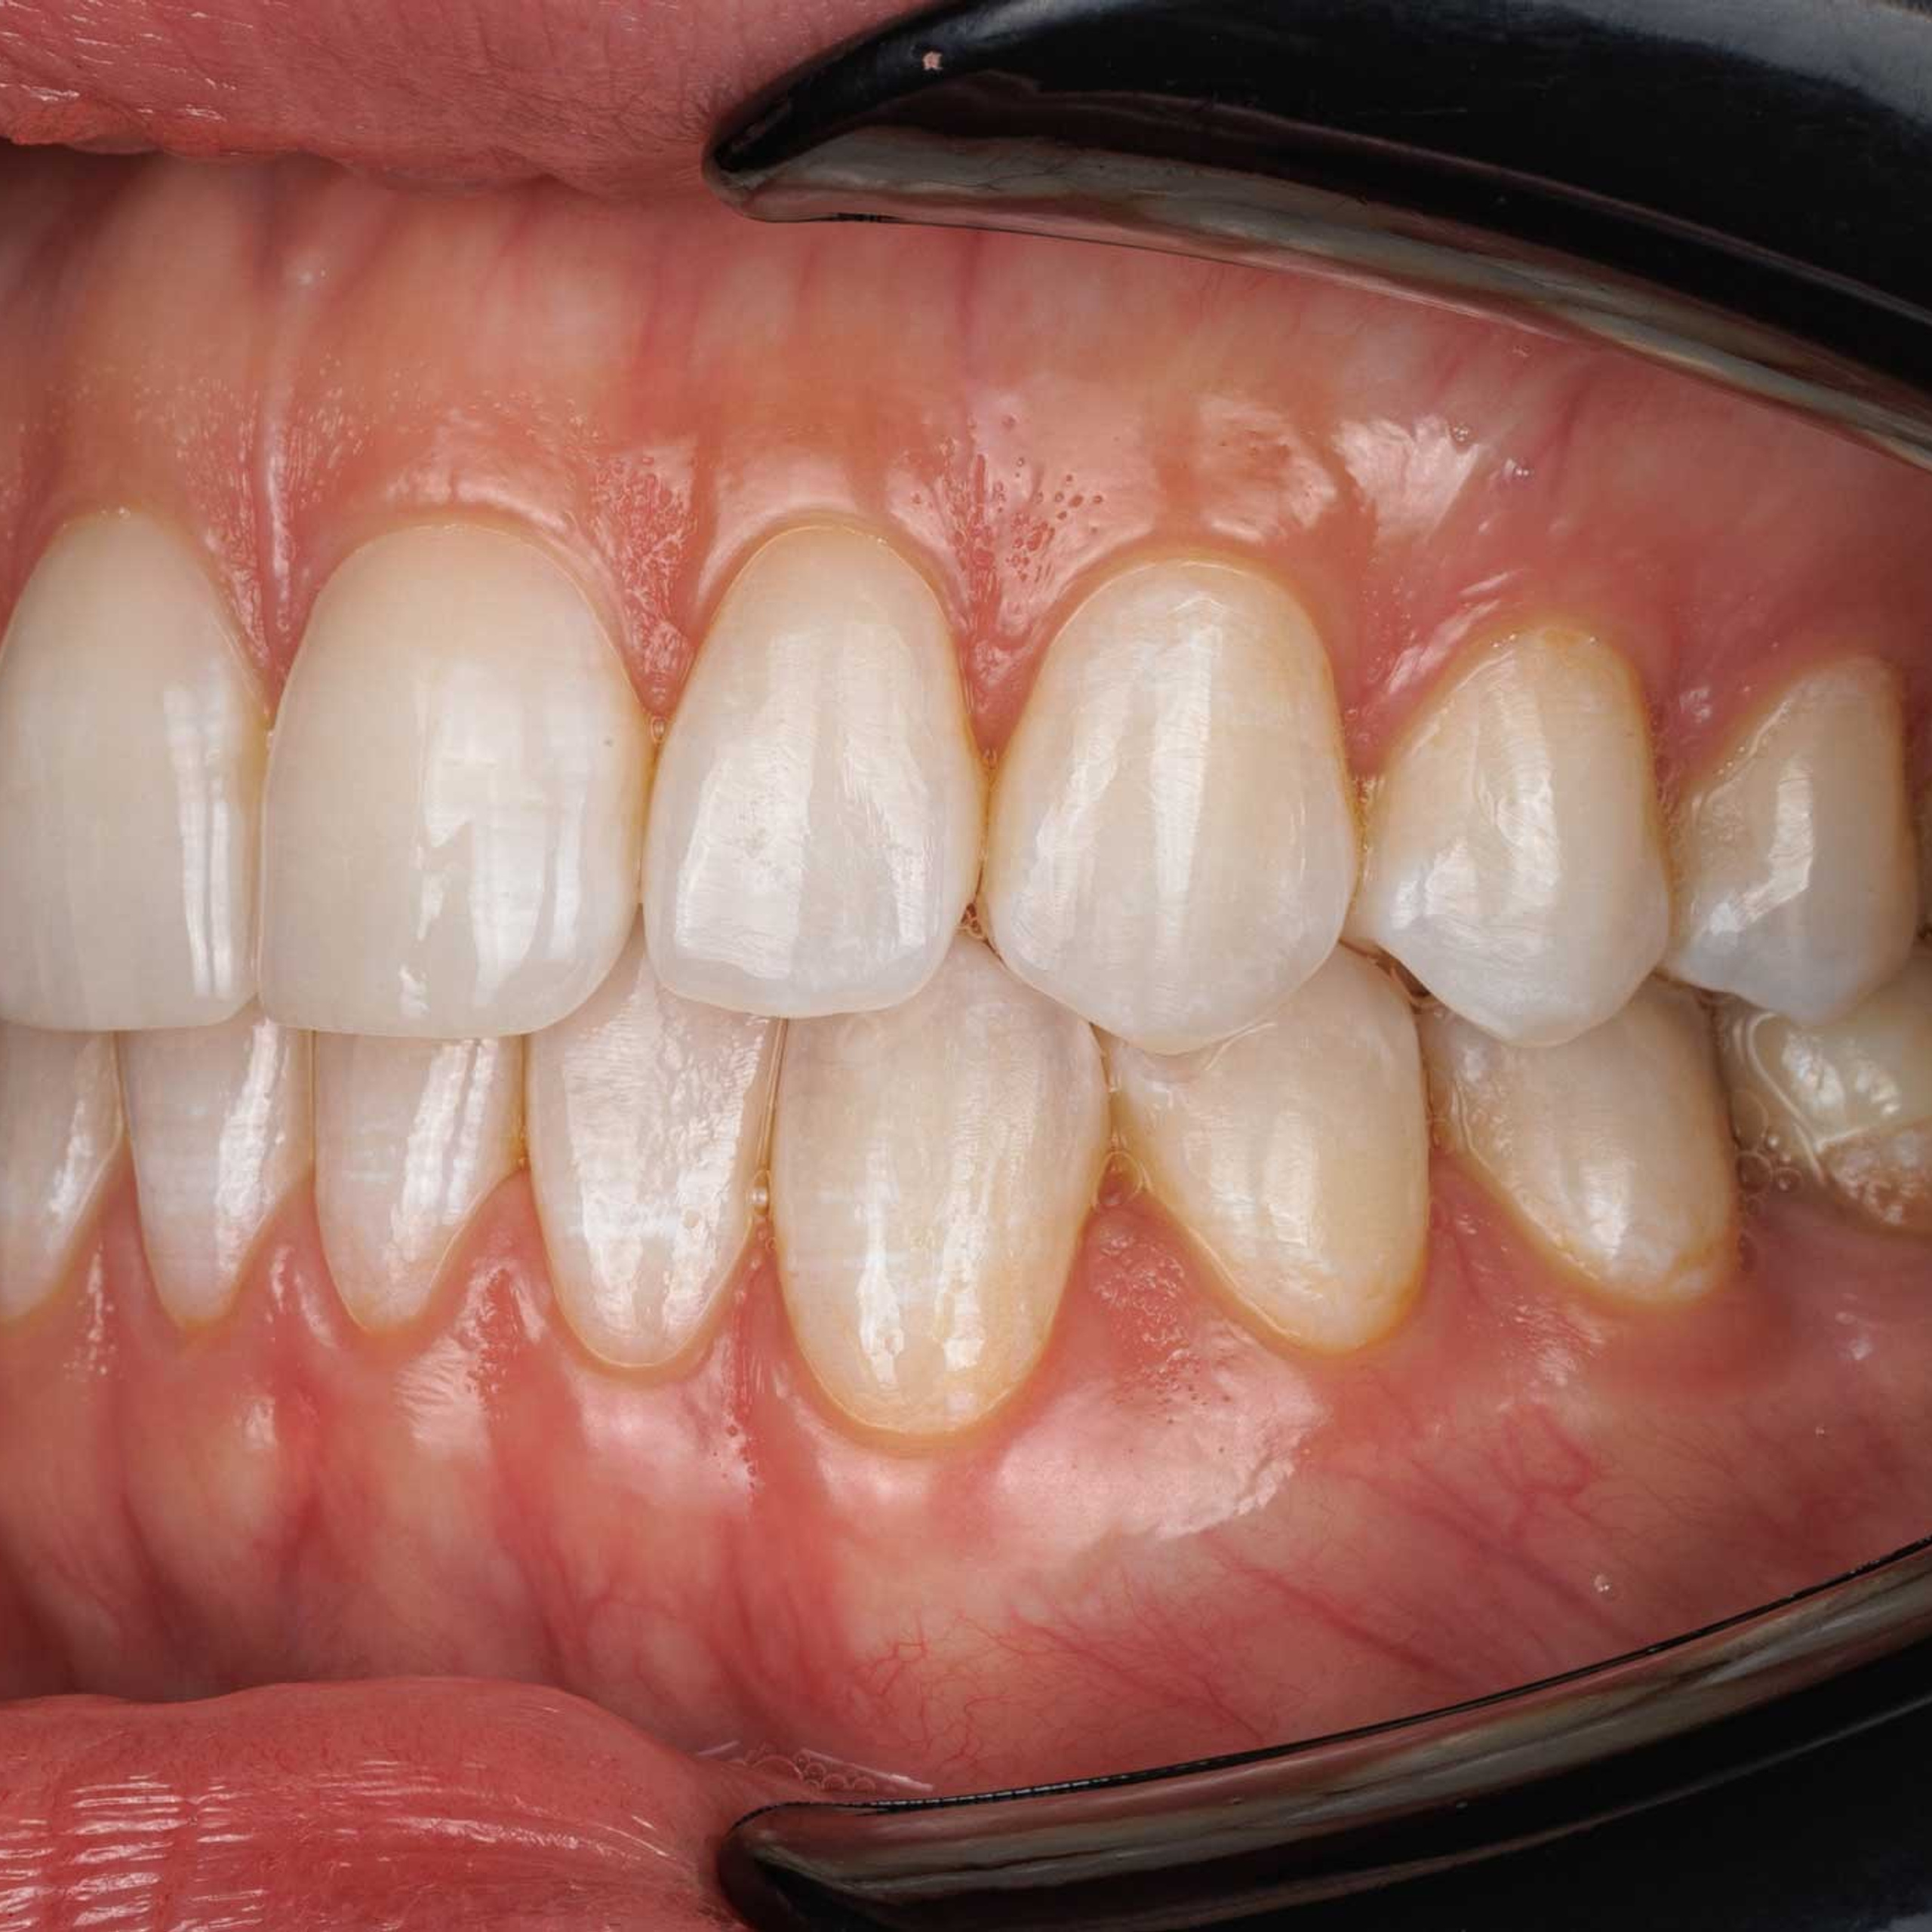

Фотографии учеников до обучения

Фотографии после обучения